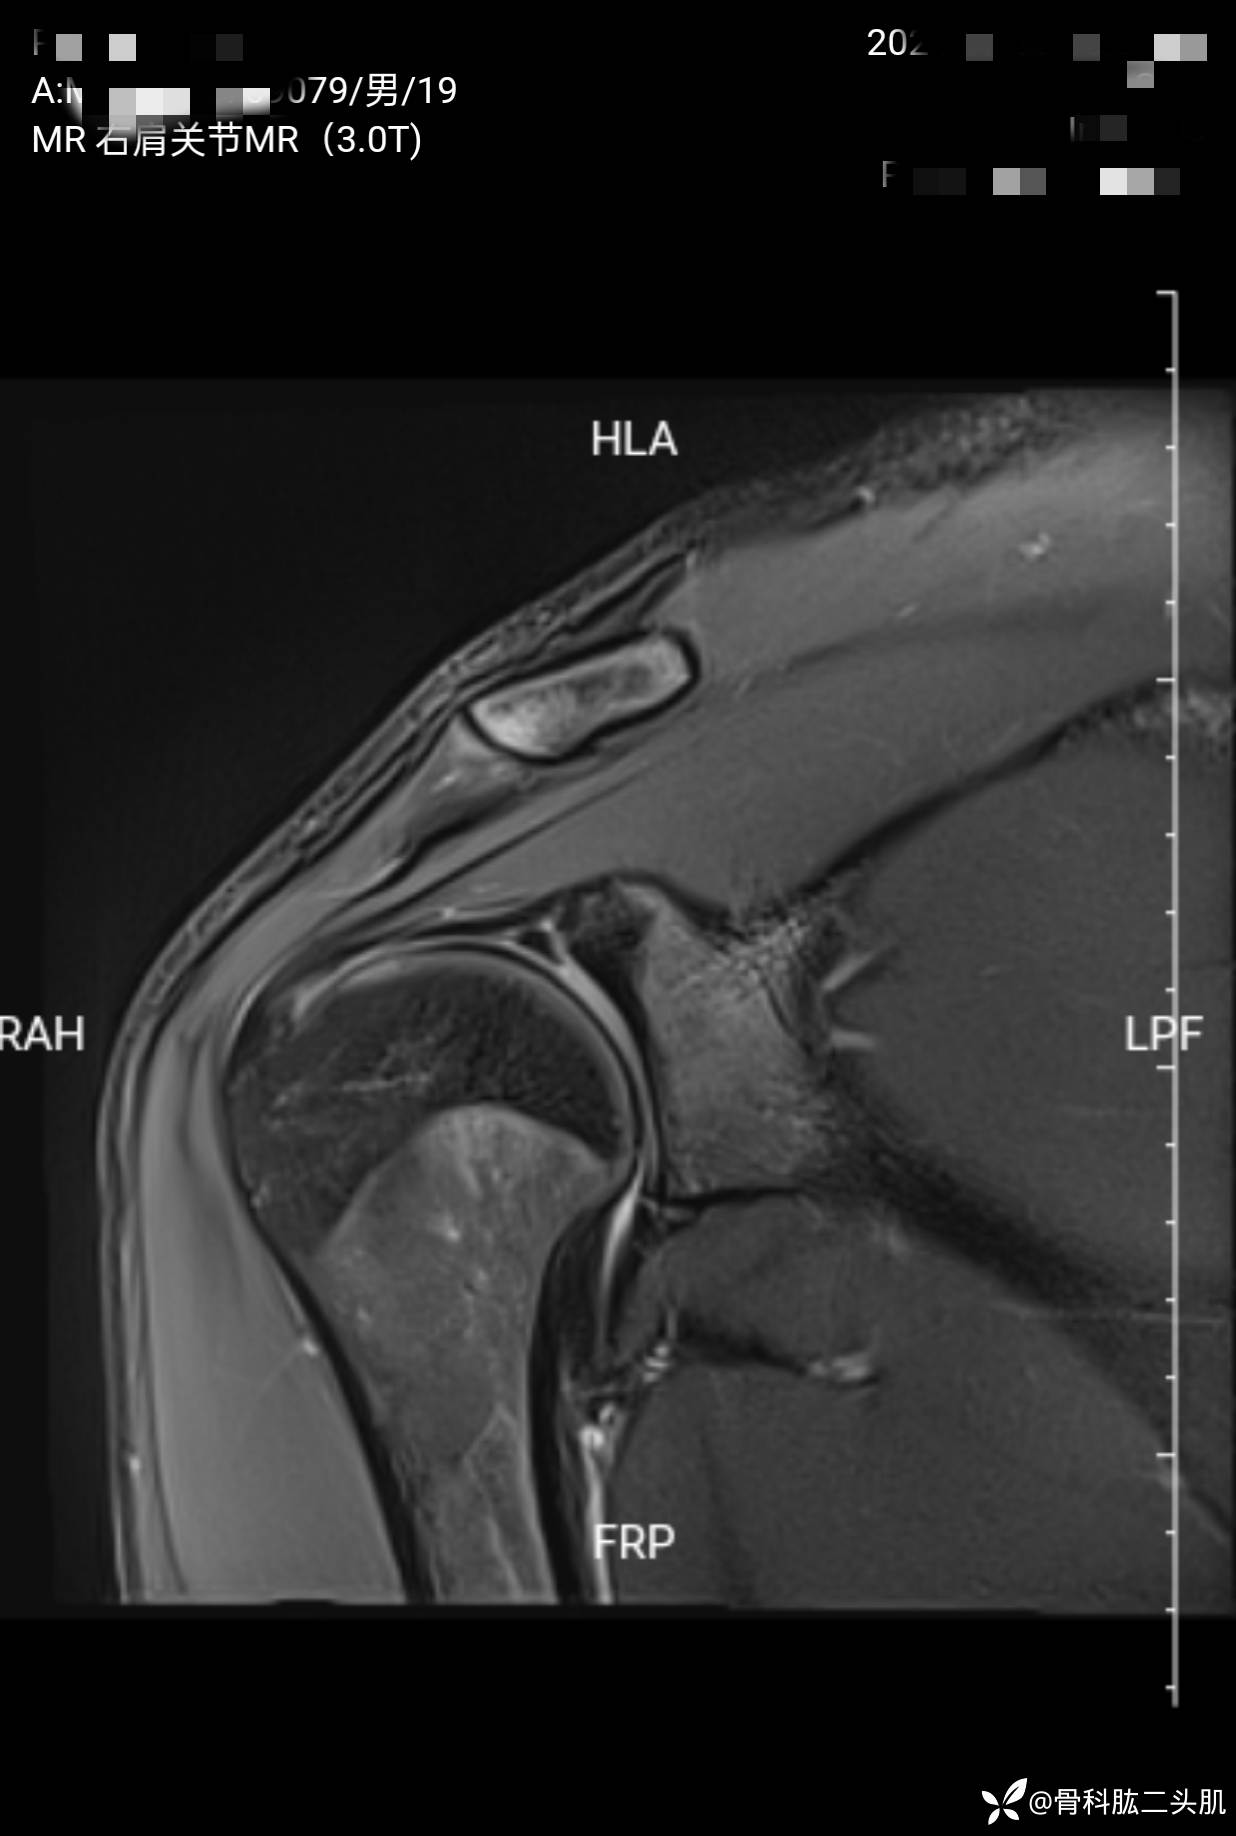

【患者信息】:患者男19岁

【主诉】:右肩关节复发性脱位2年

【检查】:外院核磁示 :右肩前盂唇及上盂唇损伤可能;右肩肱骨头后上缘骨质凹陷;右肩冈上肌肌腱损伤。

【临床诊断】:1.右肩关节复发性脱位 2 .右肩盂唇bankart损伤 3.右侧肱骨Hill—sachs损伤